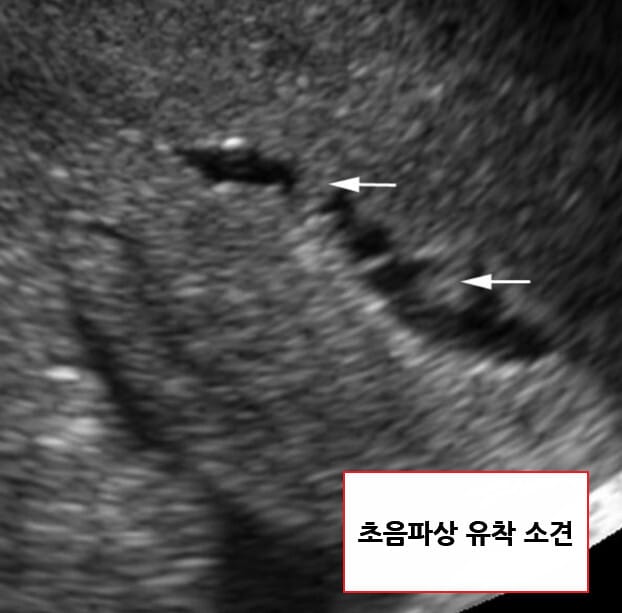

| 초음파자궁조영술(Sonohysterography) |

| -자궁강 내 불규칙한 음영 결손과 부분적인 협착 소견이 나타납니다. |